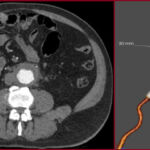

Ανεύρυσμα κοιλιακής αορτής: Mε stent-graft

Η ενδαγγειακή αποκατάσταση ανευρύσματος κοιλιακής αορτής με stent-graft είναι ελάχιστα επεμβατική μέθοδος κατά την οποία τοποθετείται ειδικό ενδομόσχευμα στην αορτή για την απομόνωση του ανευρύσματος.